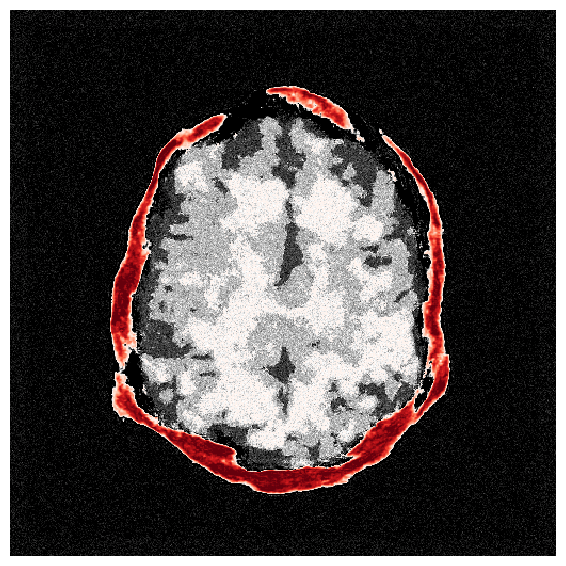

To overcome the end-to-end inference problem, we apply one iteration of ASPIRE by training a CNF on pairs, , where the ’s represent the score-based summary statistics at the fiducial points, , taken to be the uniform water velocity for all samples. An example of this initial summary statistic is shown in Figure 8. While the outer edge of the skull is reasonably well delineated, the inner edge of the skull is still poorly resolved and details inside the skull are mostly absent. However, the inference based on these initial summary statistics, shown in Figure 9, present a significant improvement over the baseline (cf. Figure 7), despite the presence of strong imaging artifacts in the summary statistics. The improvements concern the skull’s structure in particular, although details within the skull remain elusive due to the summary statistic’s limited information. To enhance fidelity further, ASPIRE 2 (shorthand for ASPIRE at iteration ) is applied by recalculating the score at the new posterior mean estimate for each training sample. Given these new training pairs, the next CNF is trained. While posterior sampling is efficient with CNFs (using Equation 4), recalculation of the score for each sample is computationally intensive, a topic we address in Section 6.6.